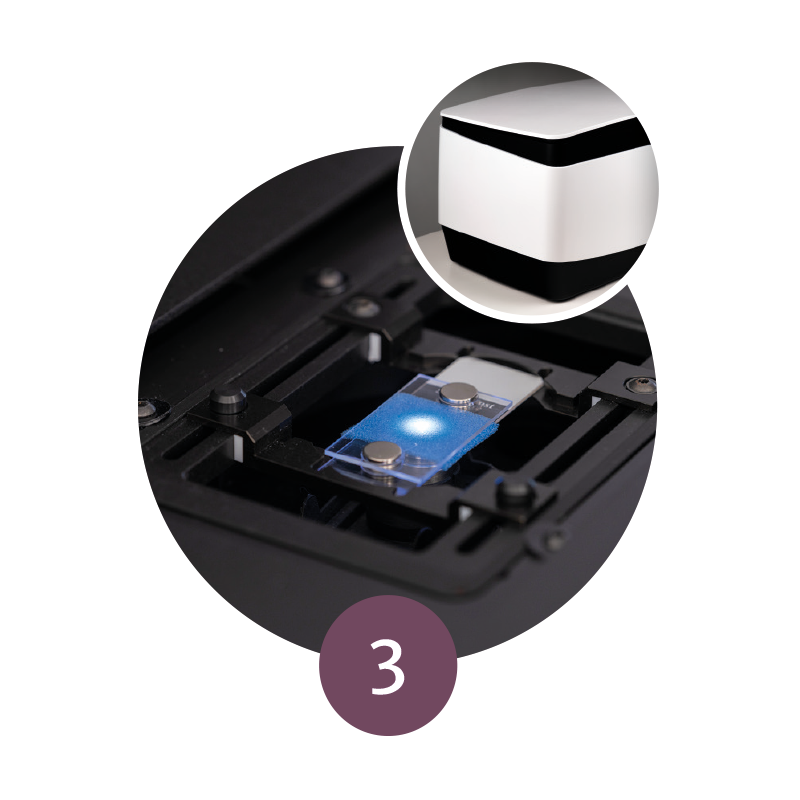

Step 3: Tissue Mounting

The glass slide is subsequently inserted into the VivaScope 2500.